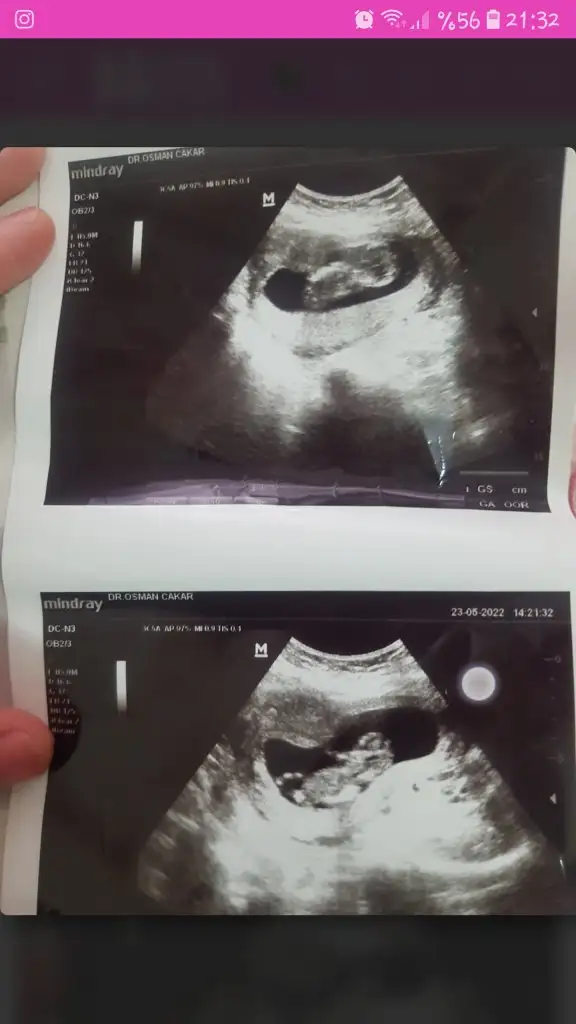

Plasenta net değil pek anlaşilmiyo8+2 karından ultrason

Bir de bu ultrason görüntüsüne bakabilirmisinizPlasenta net değil pek anlaşilmiyo